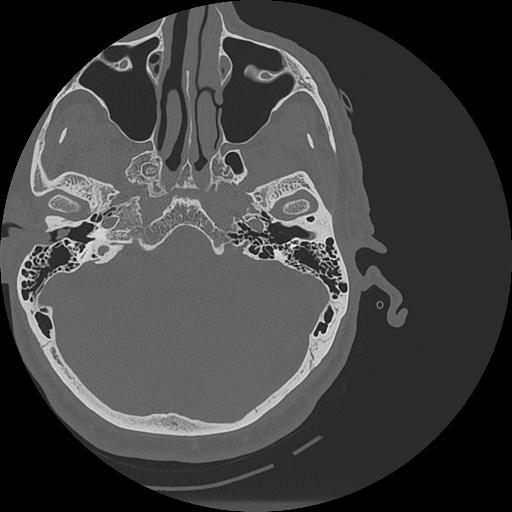

7 HUESO,,Vol,0.5,HUESO,,